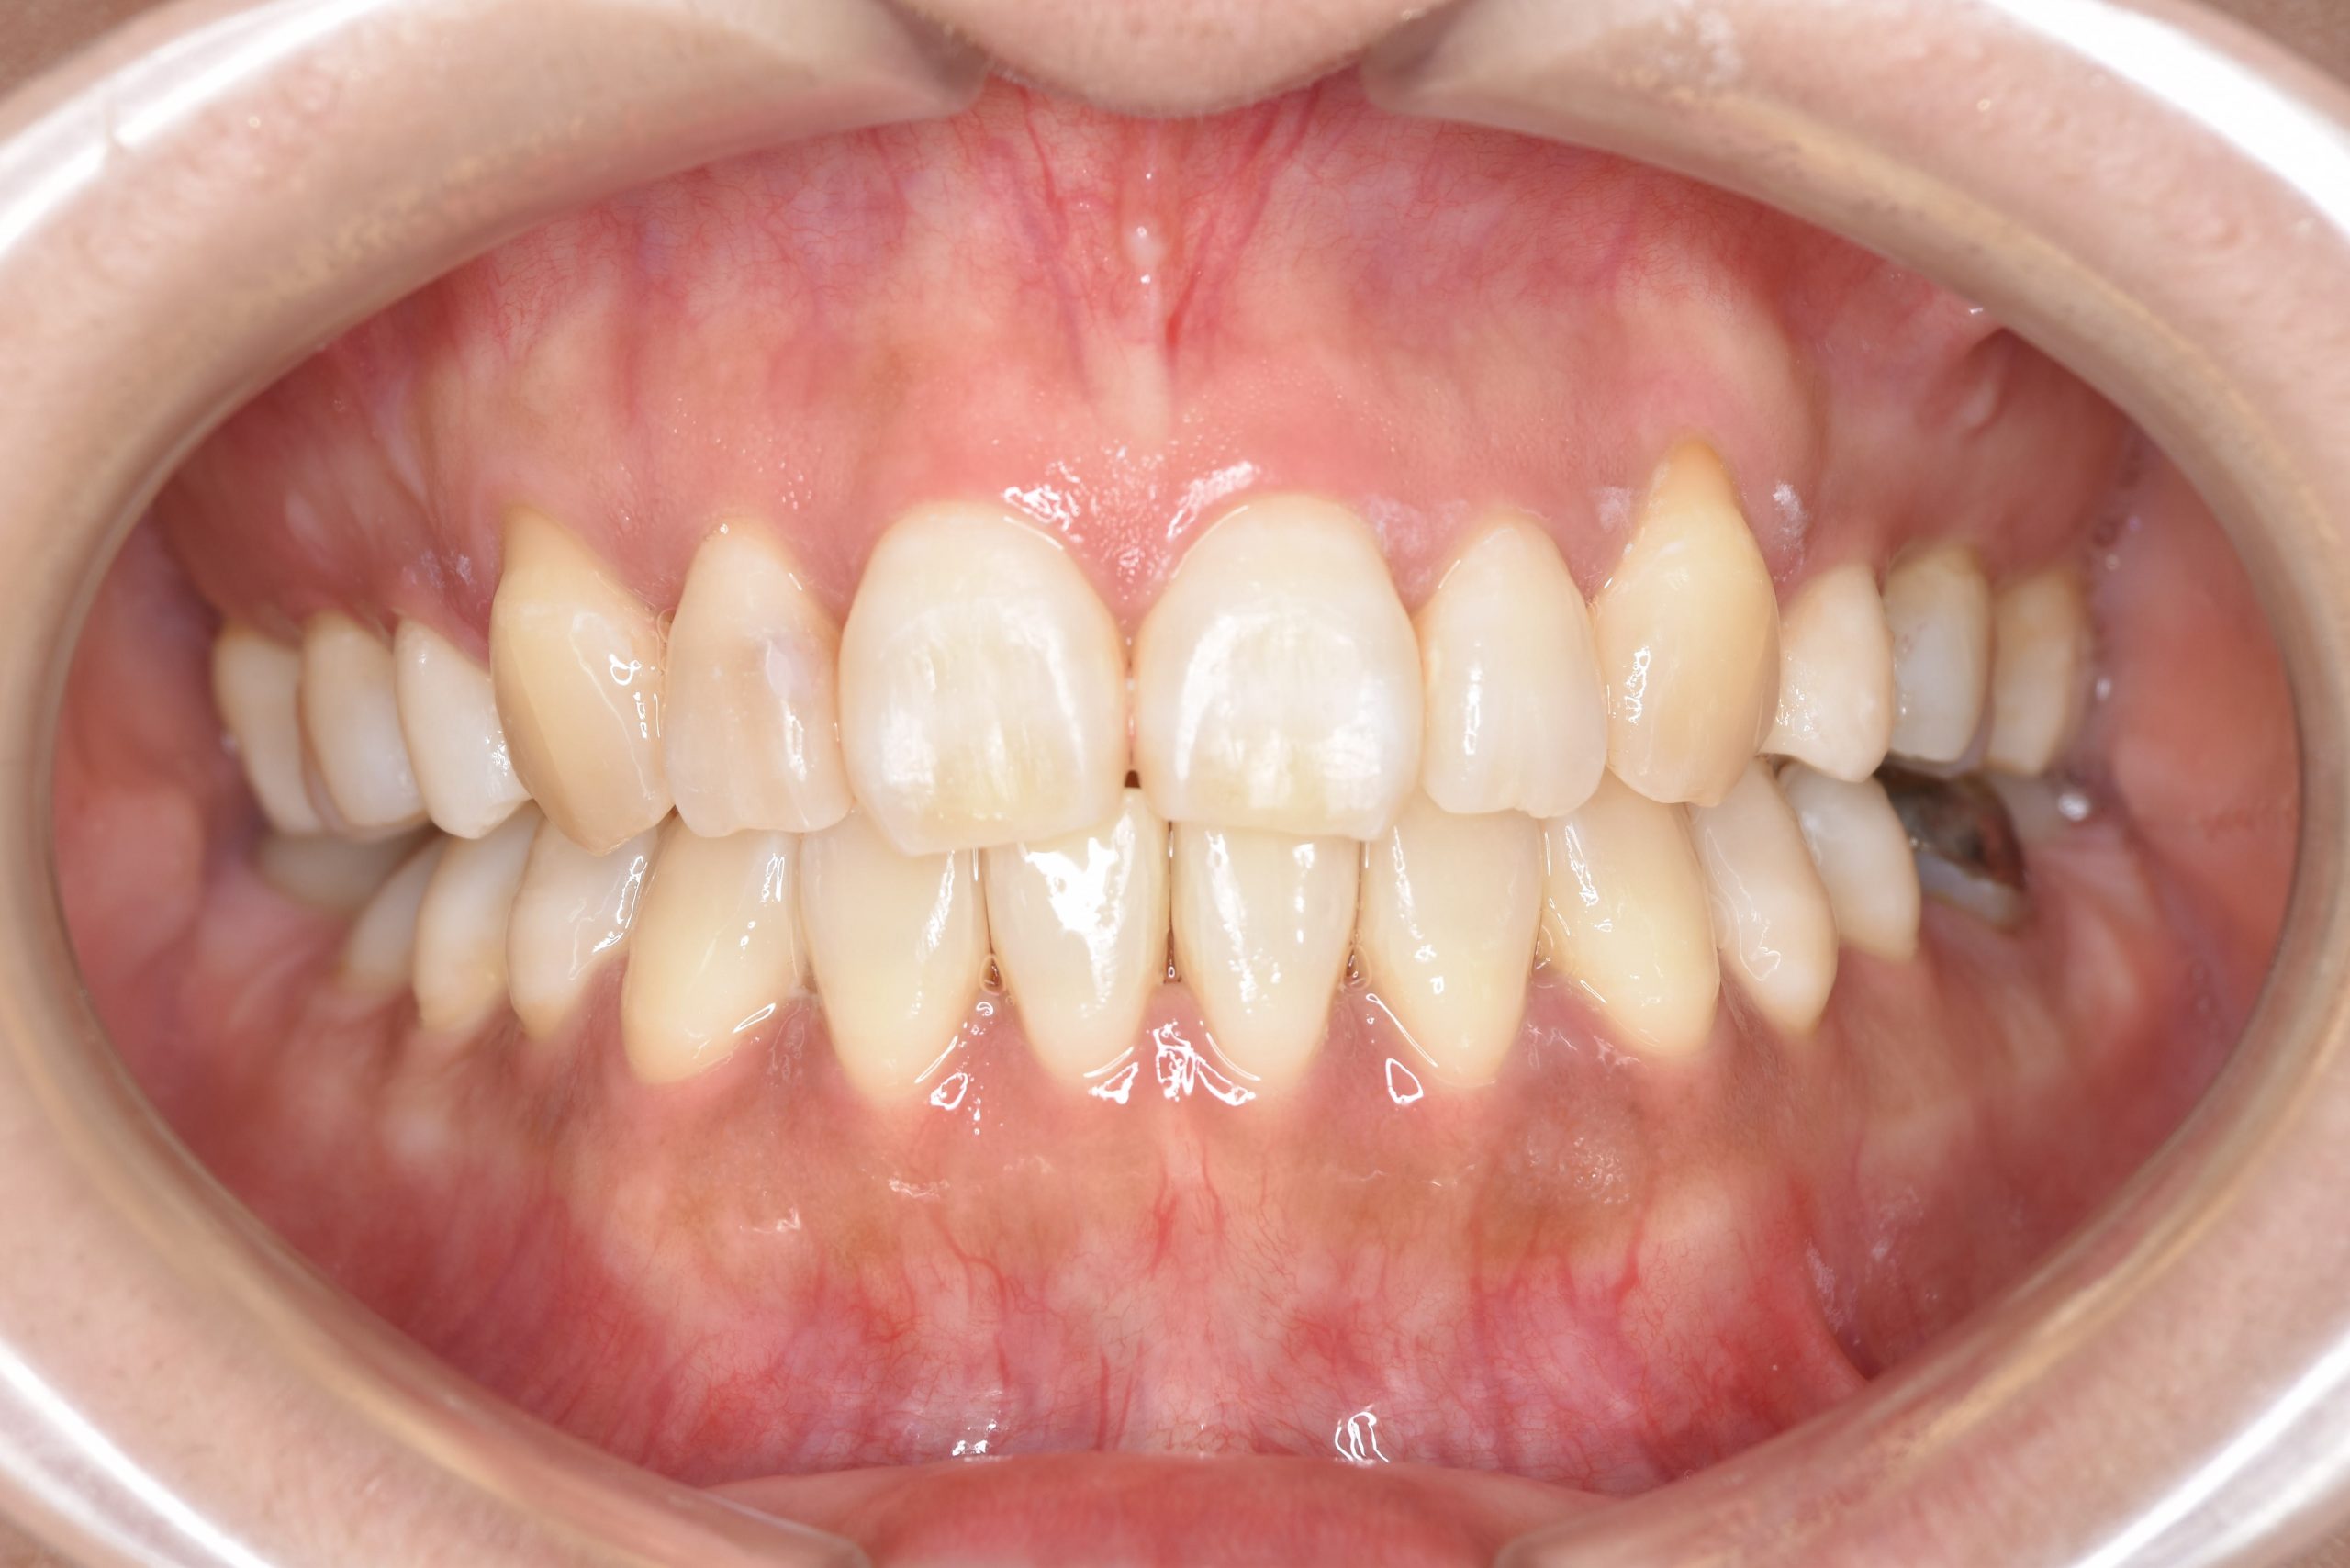

アフター

全顎ワイヤー矯正 症例_141

主訴 八重歯|上下センターがずれている

施術内容 成人矯正1期治療

治癒期間 4年10ヶ月間

費用 1,106,560円(税込)